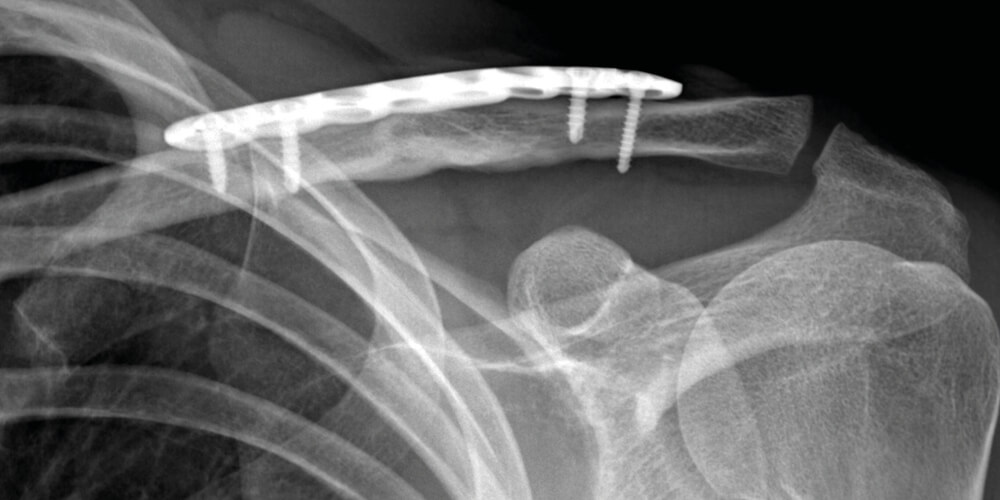

L’osteosintesi è l’intervento chirurgico, eseguito a cielo aperto, che permette di riallineare e fissare i frammenti ossei dovuti a una frattura. Tanto nel caso dell’omero prossimale, quando nel caso della clavicola, se la frattura è scomposta si procede quindi con questa pratica chirurgica, durante la quale le parti ossee vengono riposizionate e fissate tramite placche e viti o chiodo endomidollare.